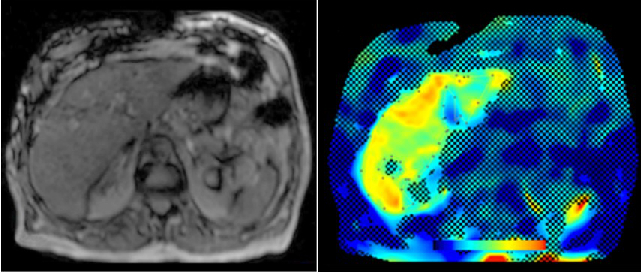

Abdominal MR Imaging

Michaela Plaikner, Benjamin Henninger, Christian Kremser

Morphological and functional MRI in all-organ systems development of novel MRI applications and MR sequences. Examples of research projects: fat, iron or combined disease; influence of iron on the evaluation of liver fat.

b) MR-Elastography (MRE)

MRE is increasingly used in hepatic MRI to detect and classify fibrosis in the early stages before morphological changes have occurred. In our department, MRE is already integrated into the routine hepatic MRI protocol and used for various research projects.